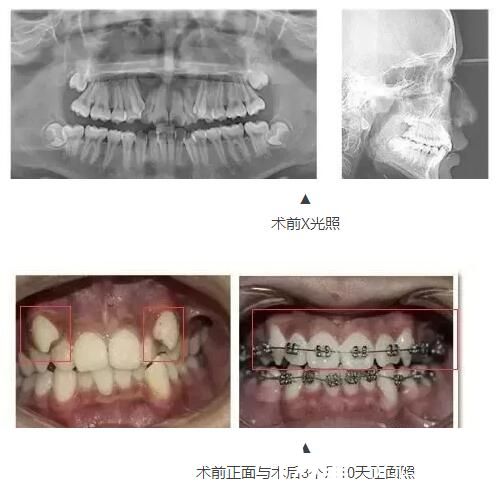

術前照片:

術后照片:

案例一:16歲中學生牙齒矯正

16歲中學生樂樂一直是老師眼里的好學生。然而讓他頭疼的是,由于自己以前的不良習慣,導致現(xiàn)在的牙齒不齊,甚至不敢開口露出牙齒。

三個月前,小斌通過朋友的推薦,來到泰州麗都醫(yī)院,希望醫(yī)生可以還他一口整齊的牙齒。醫(yī)生給他制定了金屬托槽矯治方案。小斌正式成為牙套族,但讓他吃驚的是,三個月后他前來檢查牙齒,牙齒已經(jīng)發(fā)生了翻天覆地的變化!